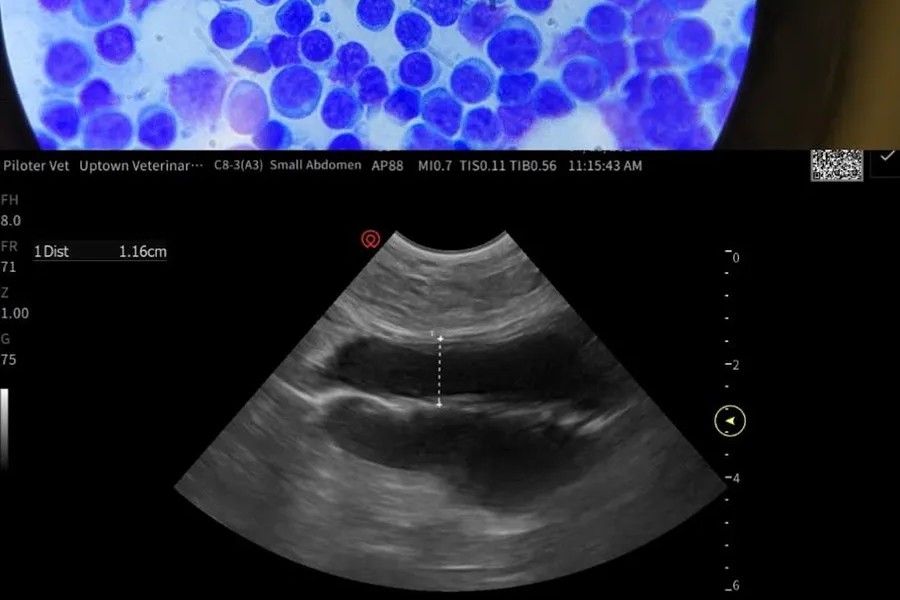

Ultrasound

Ultrasound is a non-invasive imaging tool that allows us to view your pet’s internal organs in real time. It is commonly used to evaluate abdominal structures such as the liver, kidneys, bladder, intestines, and spleen. In other situations, ultrasound may also be used to assess the heart or look for fluid within the chest or abdomen. This imaging tool provides detailed information about soft tissues and is often used alongside other diagnostics to help guide diagnosis and treatment planning.